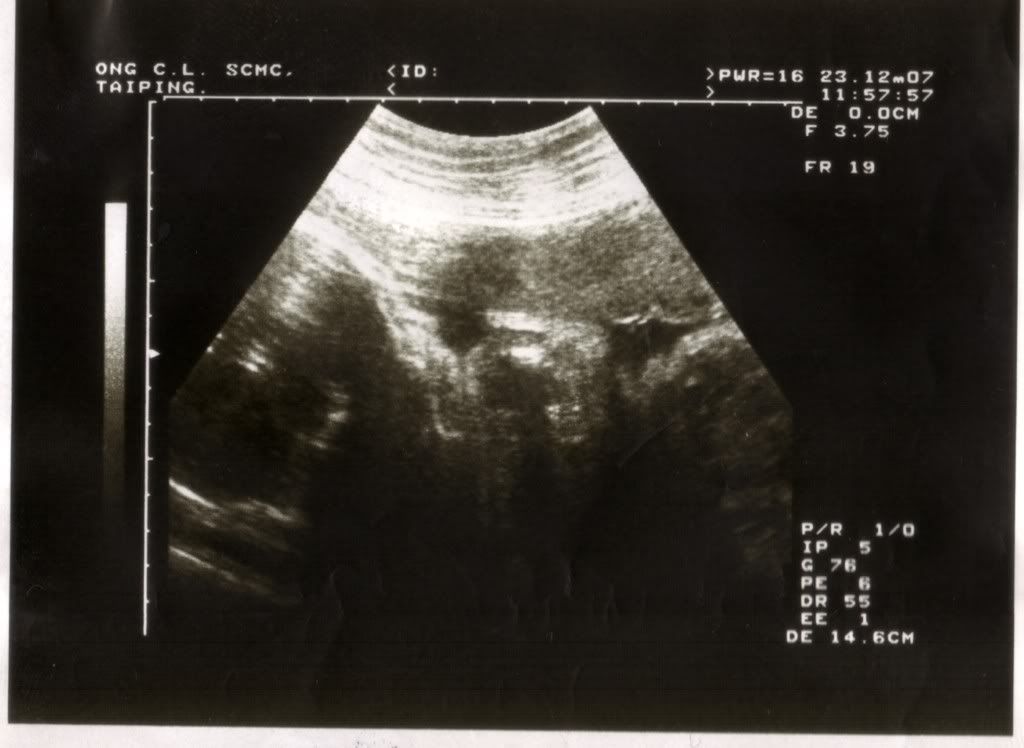

23/12/2007 31周 - 私人诊所产检

医生:halo,有什么事没有? 我 :没有,都好好..... 医生:你不要吃那么多咯!已经70kg++咯  (还比7的手指+这样的patttern-->(  ) 医生:好,去后面,我帮你scan看baby 医生:嗯,你看胎盘都上到7788了,很好。应该没有问题了. 我 :我每天有喝anmum+protein,是不是这个原因让我肥那么多啊? 医生:anmum你一天喝多少杯? 我 :2杯 医生:那么你一天一杯好了 我 :ok